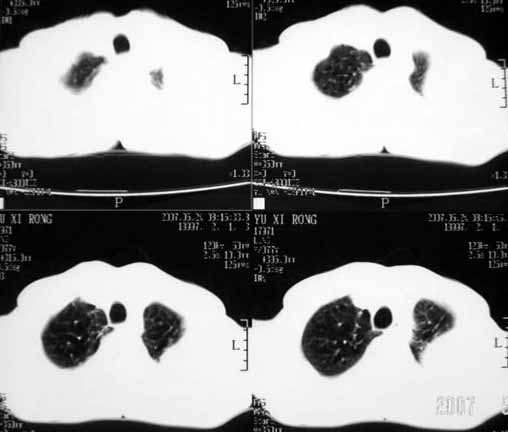

以下是引用luochengyi在2007-5-24 14:33:00的发言:[br]考虑左下肺癌。左侧胸腔积液。

以下是引用adams在2007-5-24 17:12:00的发言:[br]支持“考虑左下肺癌,左侧胸腔积液,建议胸水检查”。[br] [br]

以下是引用fumaogui在2007-5-24 16:20:00的发言:[br]左侧胸腔积液.[br]左下叶不张考虑中心型肺癌[br]建议纤支镜检查.